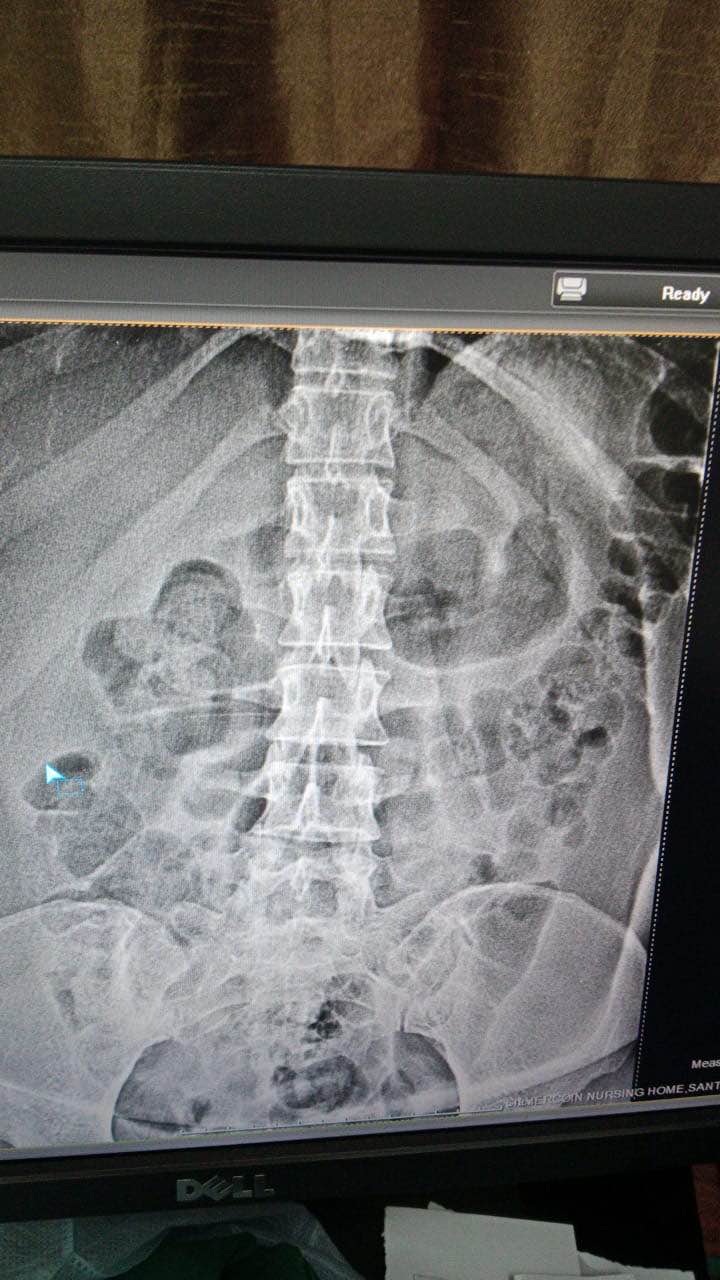

Best SPINE SURGEON IN MUMBAI